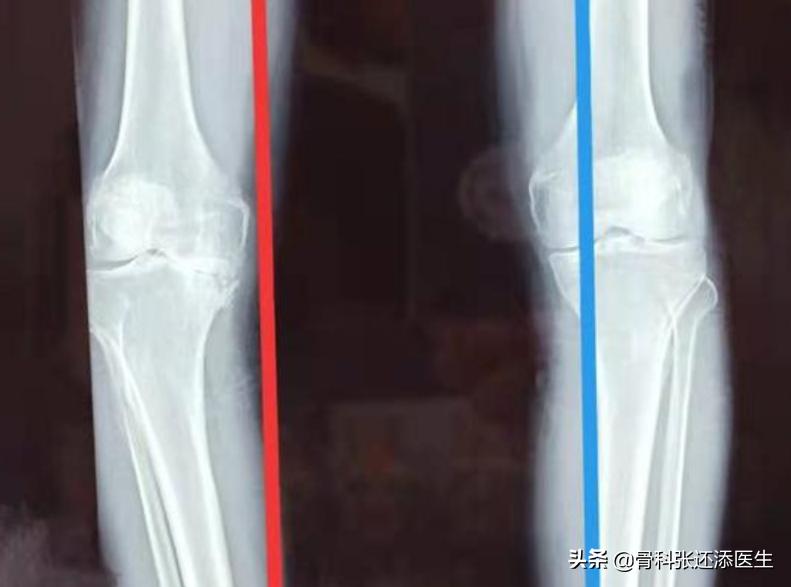

左边(红色侧)严重的关节间隙狭窄

x光表现:明确的关节间隙狭窄,有中等量的骨赘(中等量还真不好比喻。。。),软骨下骨骨质轻度硬化,可能出现膝关节骨性畸形。

x光表现:严重的关节间隙狭窄,大量的骨赘,明显的软骨下骨硬化,明显的膝关节骨性畸形。